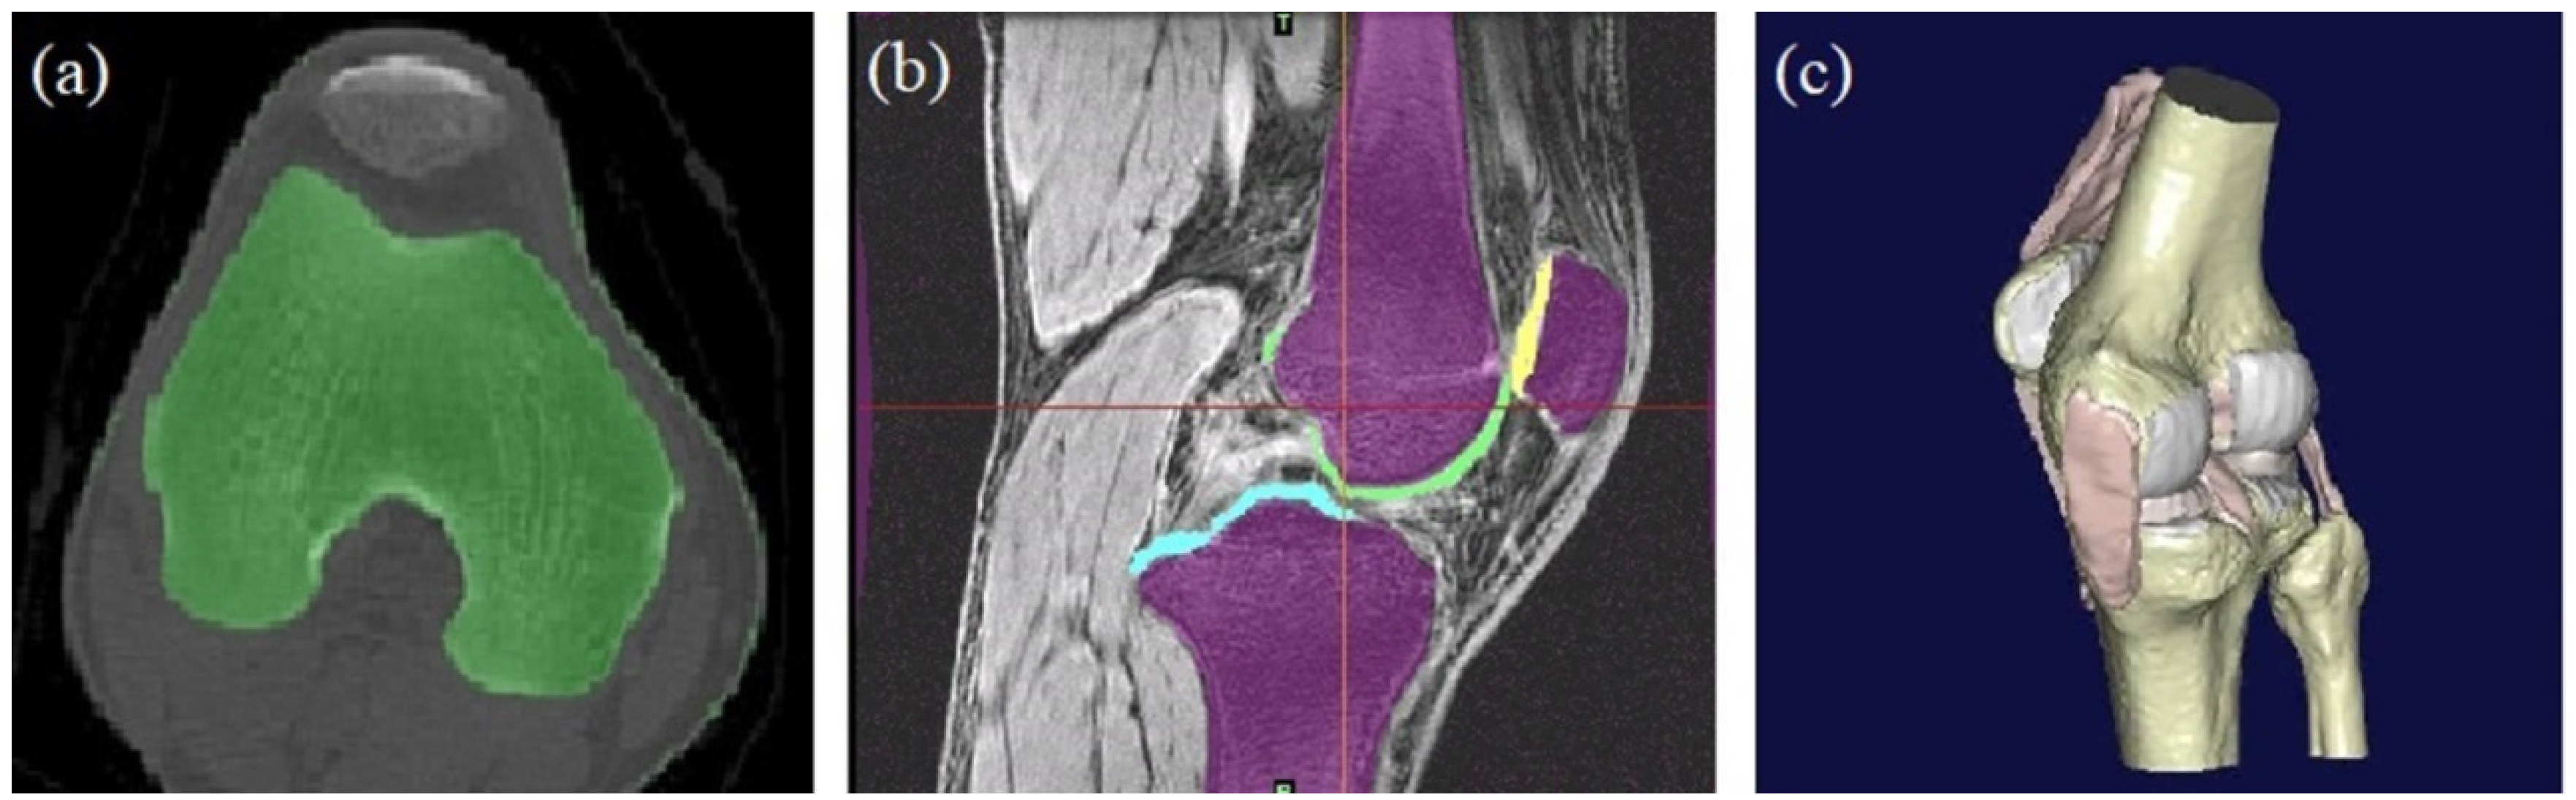

2.1. The Establishment of a Finite Element Model